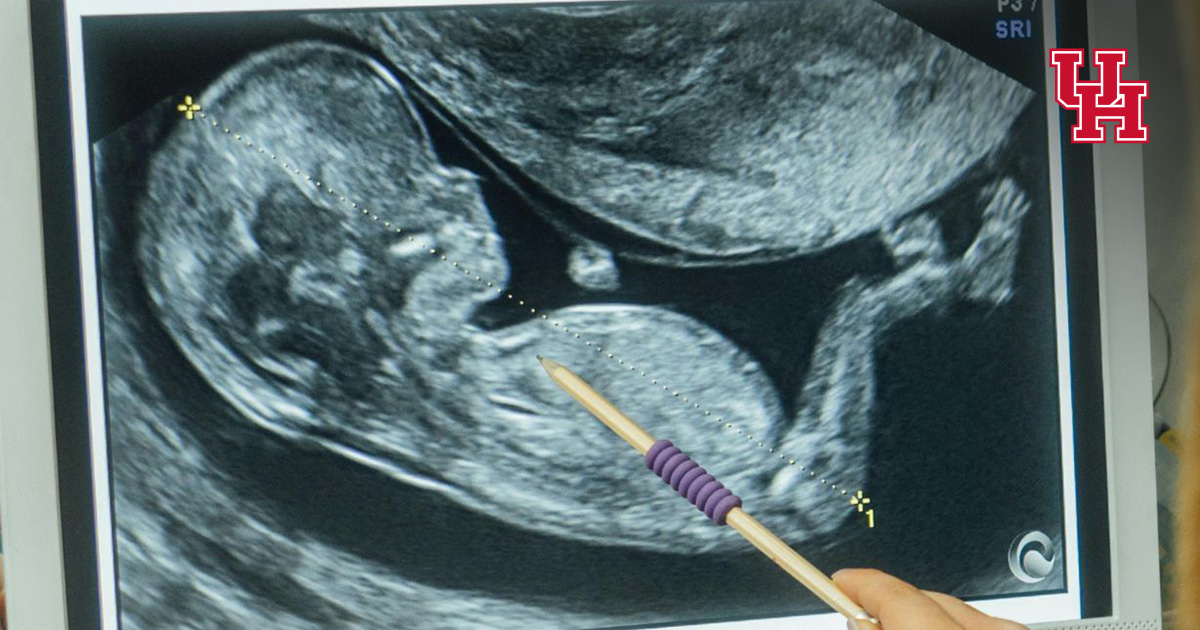

The disease, the third-most prevalent pediatric heart disease, develops when the heart’s

left ventricle develops improperly, becoming spongy and thick rather than smooth and

firm. This causes an inability in the heart to contract and relax properly and to

efficiently pump blood.